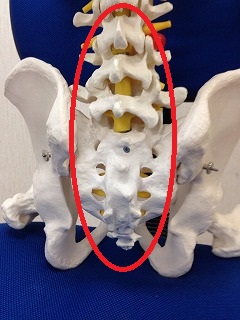

股関節やお腹の奥の筋肉も硬い感じがしました。

体が前傾気味で丸くなってしまっていて膝に負担が出て

体が丸くなってしまうと膝がちょっと伸びづらくなってしまって

お尻周りをゆるめて股関節まわりを動きやすくして、お腹の奥の筋肉をゆるめて

足全体を動きやすくしました。

DRTを使って背骨の全体の調整をして動いてもらうと